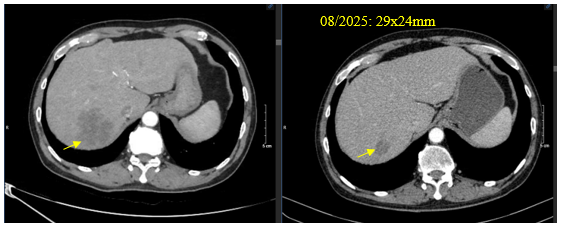

Chụp cắt lớp vi tính bụng: Tổn thương gan phải giảm kích thước: 45x47mm

Hình 2. Hình ảnh khối nhu mô gan phải – tổn thương di căn